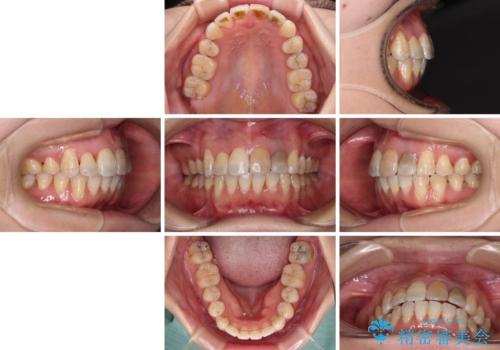

内側に転位していた歯はきれいに歯列に収まり、清掃性が著しく改善しました。

元々神経の失活してしまっている前歯2本は変色が目立つようになってきたため、今後セラミッククラウンによる補綴治療を行う予定です。